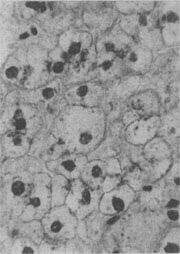

肝细胞气球样变

图1-17 肝细胞气球样变

病毒性肝炎时,肝细胞明显肿胀,胞浆疏松呈气球样